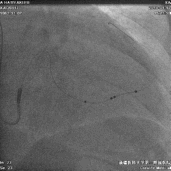

尝试导丝送入靶血管远端

● 尝试导丝先行,能否走到靶血管远端。

电极植入

● 延PTCA导丝送入电极至远端。